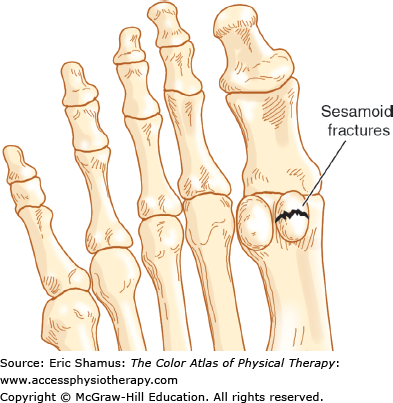

Sesamoiditis

Scenario: Patient is a 56-year-old plumber. Two weeks ago he was working in a tight area under the sink and had his ankle dorsiflexed with all of the weight on his forefoot. The toes were all into extension. When he stood up he had pain under his big toe from what he described as an over stretching. He tried to put some ice on his foot. He presents with decreased motion at the first metatarsophalangeal (MTP) joint with swelling. He is having difficulty pushing off on the foot when trying to go up the ladder. Upon palpation he is point tenderness at the flexor hallicus longus and both sesamoids.

Answer with rationale: A. Decreased push off because of the discomfort of pressure under the big toe. Increased supination and external rotation of the foot, forefoot abduction and lateral whip. These alterations come from the attempt to release pressure on the great toe and normalize the gait pattern.